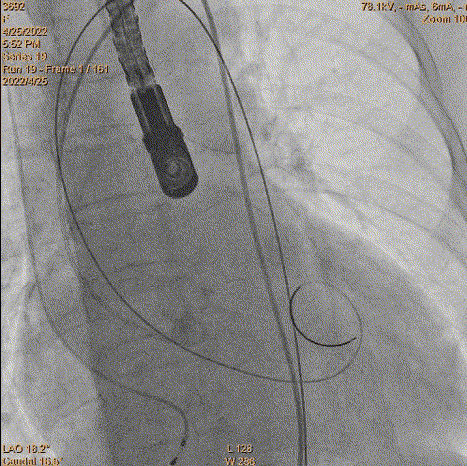

5、瓣膜定位和释放:参考猪尾中段1/3作为起始点。由于猪尾未到达窦底,参考1/2,参考Cusp overlap角度。造影确认位置,开始释放,1/4圈满满释放前1/3,起搏140bpm,压力逐步下降。

瓣膜定位评估

瓣膜释放

评估深度

评估深度-过深

6、瓣膜回收和再释放:到达2/3后小弯侧较深,经多角度评估评估较深,起搏回收再次释放。